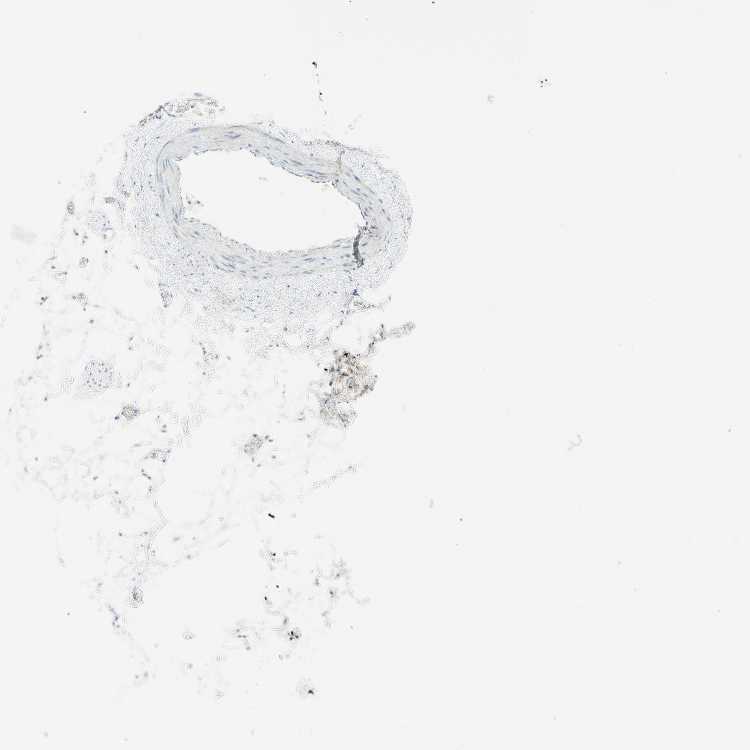

SOFT TISSUE 2 - Antibody stainingi

Antibody staining in the annotated cell types in the current human tissue is reported as not detected, low, medium, or high, based on conventional immunohistochemistry profiling in selected tissues. This score is based on the combination of the staining intensity and fraction of stained cells.

Each image is clickable and will lead to virtual microscopy that enables deeper exploration of all samples and also displays staining intensity scores, fraction scores and subcellular localization as well as patient and tissue information for each sample.

Antibody HPA011036Antibody HPA011057

Fibroblasts Not detectedNot detected

Peripheral nerve LowLow